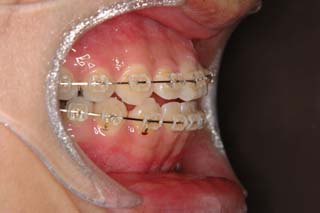

マルチブラケット装置でまっすぐに並べただけの状態です。なるほど、まるで噛めてない状態なのがよく分かります。ここでよく有りがちな矯正治療だと、上の前歯と下の前歯にゴムを1日中かけて噛ませていくのですが、それでは以前と同じく、関節をずらして噛むだけの人になってしまうでしょう。特に垂直的なコントロールが必要と考えられた上顎左側に オーソアンカー SMAPシステム の植立を行いました。

次第にアゴのズレが取り除かれて、しっくり噛めるかみ合わせに変化していっています。長い年月をかけて修飾されてきた顎関節の環境はなかなか良い形に変わりませんので、時間をかけて改善を行います。